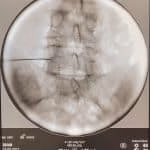

- Rizotomia percutânea lombar

- Implante de neuroestimulador medular